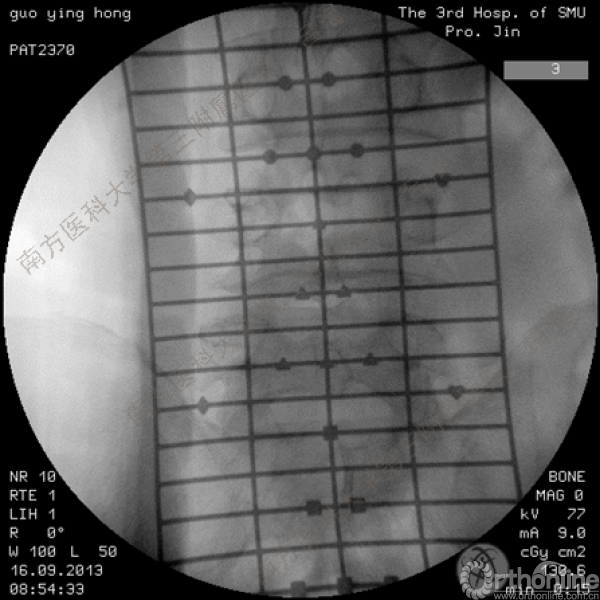

随着社会老龄化进程加快,胸腰椎退行性病变的治疗已经成为脊柱学术界的一个热点话题。MIS-TLIF手术可以治疗多种不同的胸腰椎退行性疾病,南方医科大学第三附属医院吕海教授结合病例为我们一一展示了该术式在治疗不同胸腰椎疾病时的具体手术过程。